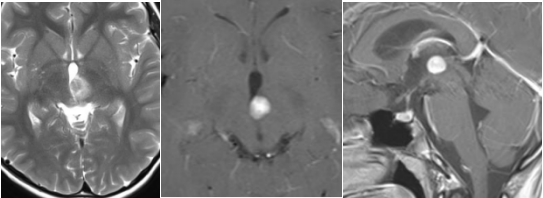

11岁的明明,3个月前因在家捡拾桌底物品碰到头部,当时没有任何事情,然而二天上学出现强烈头痛、头晕。父母以为头撞坏了,紧急赶往医院,MRI核磁检查结果提示:左侧丘脑占位性病变,考虑肿瘤性病变,生殖细胞瘤可能性大。头痛、头晕当日就缓解了,而且并未出现其他不适。但是孩子脑子里的肿瘤成为父母心中的较大隐患,半个月后前往北京某医院完善MRS,专家建议进行穿刺活检。医院专家结合影像和其他资料,初步判断为低级别星形细胞瘤,建议手术治疗。目前明明已无头痛、头晕状况,精神状态良好,各项学习、生活状态均正常。为了让孩子得到更好的治疗,他寻求国际神经外科手术教授的治疗意见:孩子都好,可以不手术吗?或者进行质子治疗?如果要手术,是否可以全切?手术风险和可能会发生的术后并发症有哪些?以及发生几率是多少?可以不去德国,等巴教授来国内手术吗……

在本月晚些时候进行MRI复查后,我们仍然可以讨论手术的必要性。在这种情况下,我能够顺利,完整地,通过显微外科手术切除附图上看到的这种位置,形态和范围的病变。预计在这么短的时间内(MRI检查间隔2个月)形态不会发生显着变化。我做手术的话,手术风险会很低(暂时性复视,局部出血,共济失调)。语言,运动,认知功能在手术中不会有危险。